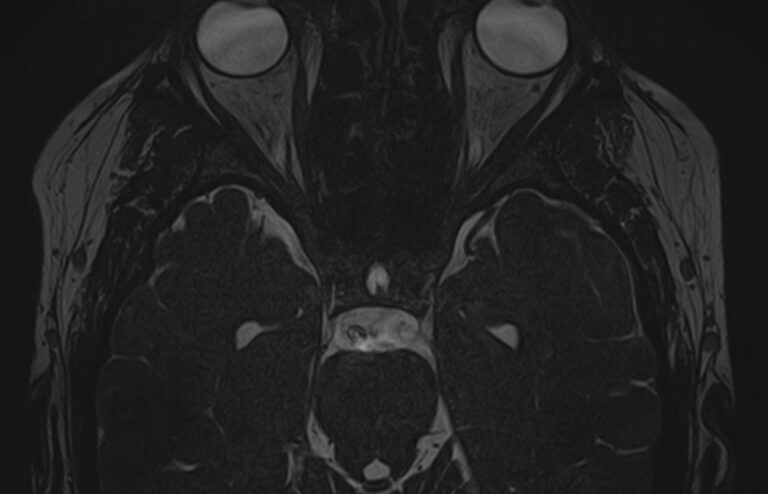

Для диагностики поражения черепно-мозговых нервов, а также оценки состояния окружающих их тканей и визуализации сосудистой сети головного мозга в клинике «Доступная медицина» проводится комплексное обследование МРТ головного мозга + черепно-мозговые нервы. Данное обследование включает в себя 2 протокола: стандартный — для оценки состояния всех структур головного мозга и специализированный — для изучения очагов поражения черепных нервов.

Оба исследования выполняются на современном высокопольном томографе экспертного класса TOSHIBA VANTAGE TITAN 1,5 Тесла, который использует разные режимы сканирования с толщиной среза от 1мм в различных плоскостях с последующей цифровой обработкой полученных данных для создания трехмерных изображений. Аппарат позволяет выявлять структурные изменения в веществе головного мозга и черепных нервах уже на начальной стадии, когда другие методы не дают результатов.

• патология нервов на фоне сосудистых проблем (вазоневральный конфликт — сдавление нерва близлежащим сосудом, также на фоне патологической извитости, аневризмы, сосудистой мальформации).